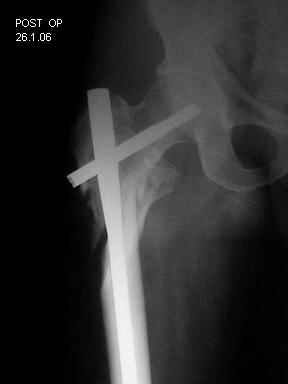

I choose Long Gamma Nailing and did it on 24.1.2006.

Now posting the post op x-rays for all of yours comments please. Don't hesitate to criticize me.